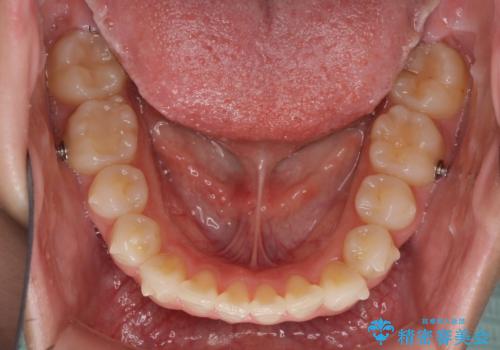

- デコボコと飛び出した前歯を治したいとのことで来院された患者様です。

ゴムかけを活用して上顎歯列全体を後方移動し、IPR(歯と歯の間を削る)によってデコボコが解消するように設計し、インビザラインにより治療を行うこととしました。

毎日しっかりと装着してくださったので、概ねシミュレーション通りに歯を移動させることができました。

治療前には接触することのなかった上下の前歯が接触するようになり、食事の際前歯でものをかみ切れるようになりました。